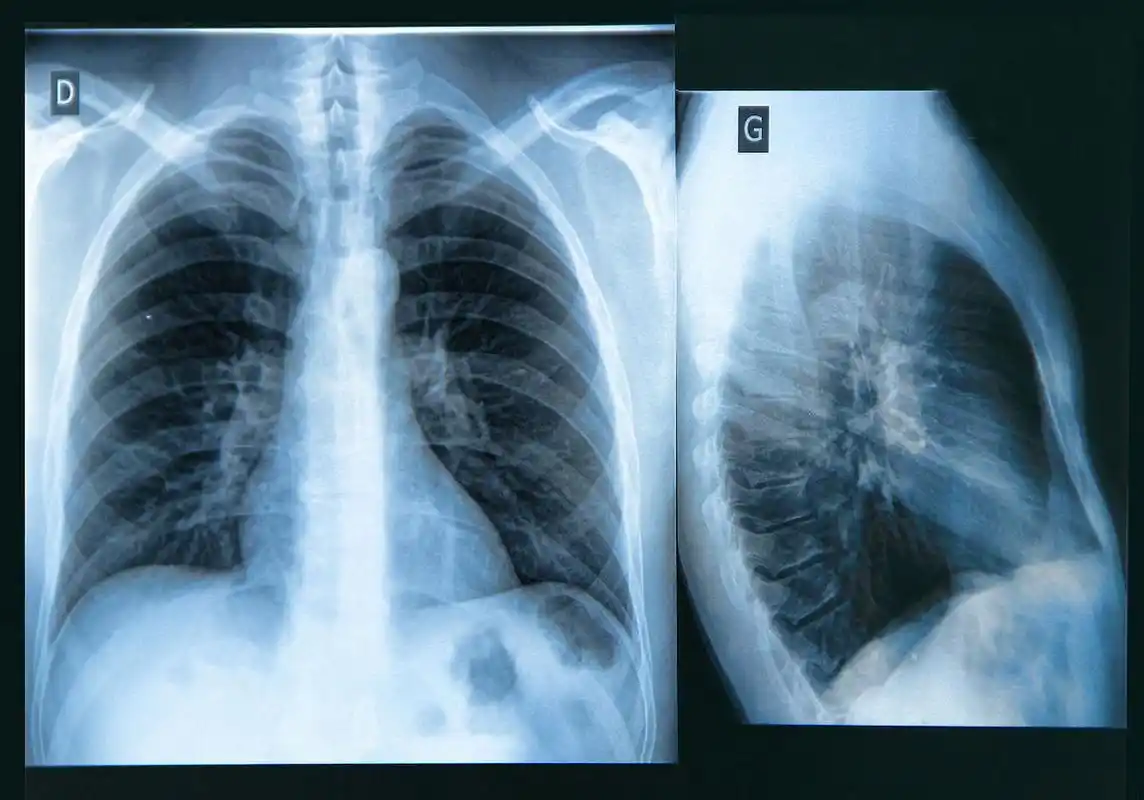

肺气肿ct典型图谱,一学就会_医学界-助力医生临床决策和职业成长